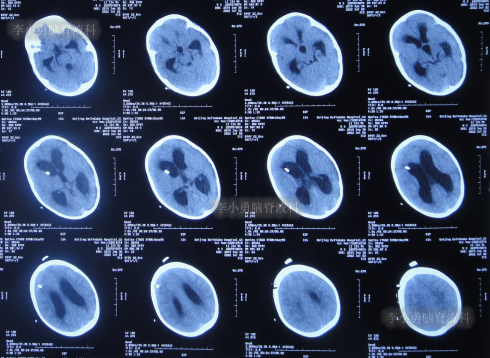

住院治疗18天即2022年7月18日,查头颅CT示脑室有缩小(图-12)。

图-12:2022年7月18日头颅CT

住院治疗63天即2022年9月1日,常规查头颅CT示脑室引流术后状态(图-15)。

图-15:2022年9月1日头颅CT

2022年10月12日(住院治疗104天),已夹闭脑室引流管3天,查头颅CT示脑室未见异常(图-17)。

图-17:2022年10月12日头颅CT